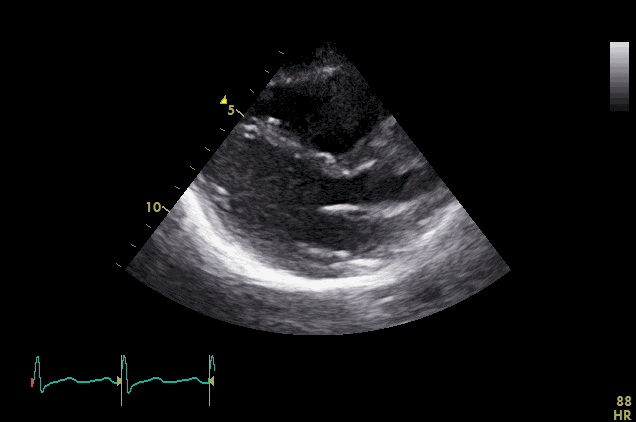

Visual Examples

PLAX Example 1 PLAX Example 2 PLAX Example 3 PLAX Example 4